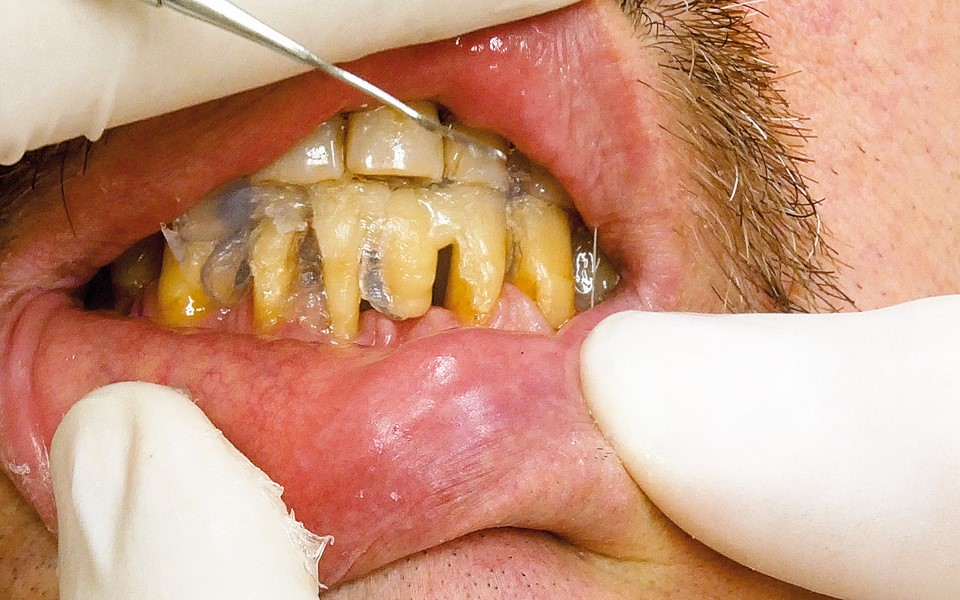

Jedną z popularniejszych metod stabilizacji zębów rozchwianych jest ich szynowanie. Metoda ta, wspierająca inne metody leczenia, jest powszechnie stosowana. Jednym z najnowocześniejszych materiałów wykorzystywanych w stomatologii do szynowania zębów jest taśma poliaramidowa. W opisanym przypadku autorzy pracy przedstawiają sposób uproszczenia całej procedury i ograniczenia ryzyka popełnienia błędu, szczególnie w sytuacji całkowitej utraty zęba. Uzyskano to dzięki zastosowaniu indeksu wykonanego z przezroczystego silikonu.

One of the more popular methods of stabilising loose teeth is to splint them. This method, aiding other methods of treatment, is generally used. One of the most modern materials used in dentistry for splinting teeth, is polyamide tape. In the case described the authors show how to simplify the whole procedure and limit the risk of making a mistake, particularly in the situation of total loss of one tooth. This was achieved thanks to the use of an index made out of transparent silicone.